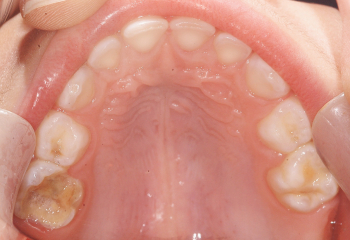

Después: